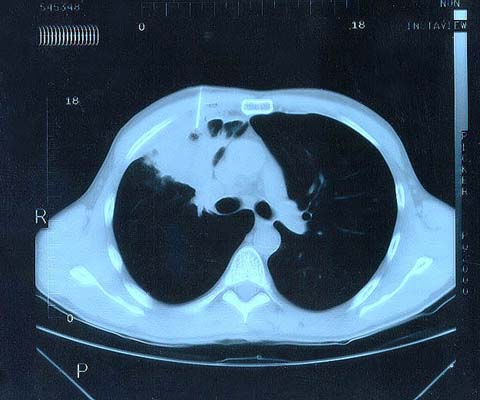

Scan 25th March 1999 No4